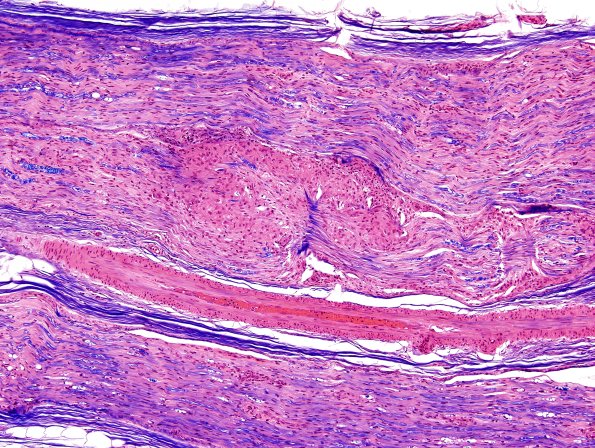

5A2-4 Additional longitudinal sections show axon loss and multiple granulomas. (H&E-LFB)